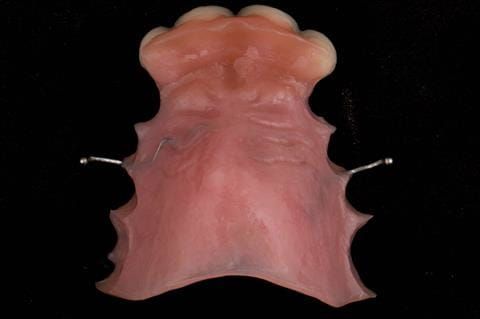

- Extract the upper 2-2 teeth and replace with an interim acrylic based partial denture. Reline the interim denture over 9 - 12 months, replacing with a definitive cobalt chromium based partial denture. The definitive denture would ideally be designed as an occlusal protective splint to reduce the the potential for mechanical wear and breakages of the moderately/heavily restored maxillary dentition. In addition, should further upper teeth require extraction they could be added on to the denture cobalt chromium framework - therefore a new prosthesis would not be required as future teeth are lost. This option would produce an excellent aesthetic outcome. This is the option the patient chose to have.

Following consultation and second discussion appointment the patient chose to have option 3 namely, a maxillary cobalt chromium based partial denture/protective occlusal splint. The clinical situation and treatment process is shown in detail below with photographs. The patient was successfully rehabilitated with this and her quality of life considerably improved. The clinical work was provided by Finlay and the technical work by Rowan.